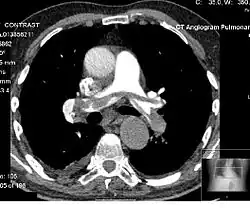

CT pulmonary angiogram

A CT pulmonary angiogram (CTPA) is a medical diagnostic test that employs computed tomography (CT) angiography to obtain an image of the pulmonary arteries. Its main use is to diagnose pulmonary embolism (PE).[1] It is a preferred choice of imaging in the diagnosis of PE due to its minimally invasive nature for the patient, whose only requirement for the scan is an intravenous line.

On CTPA, the pulmonary vessels are filled with contrast, and appear white. Any mass filling defects (embolus or other matter such as fat) appears darker. Ideally, the scan should be complete before the contrast reaches the left side of the heart and the aorta, as this may mean contrast has drained from the pulmonary arteries, or require a larger dose of contrast media.[12]

Other from assessing any filing defect within the pulmonary trunk and its segmental branches, the diameter of the right heart can be compared with diameter of the left heart. The right heart diameter should not be more than the diameter of left heart. Normally, the interventricular septum should mildly bulge into the right ventricle due to high pressure within the left ventricle. Any reverse bulge or flattening of the interventricular septum indicates pulmonary hypertension.[12]